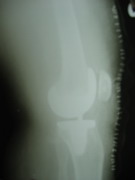

Knee Joint Replacement